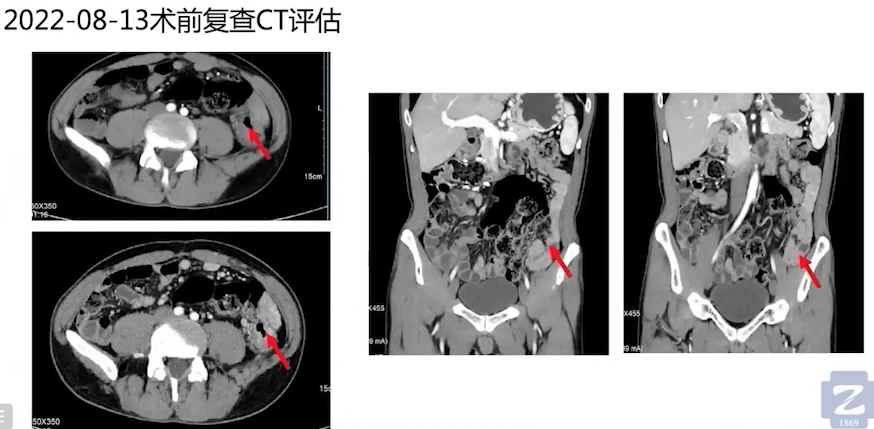

术前评估:经过3次术前新辅助免疫治疗后,2022年8月13日复查CT评估显示,左侧肿块及肠腔肿瘤明显缩小,梗阻症状明显缓解。8月16日肠镜复查,降结肠处仍可见肿块,肠腔缩窄,黏膜呈弥漫性增厚伴狭窄性改变,肠腔堵塞,进镜无法通过。